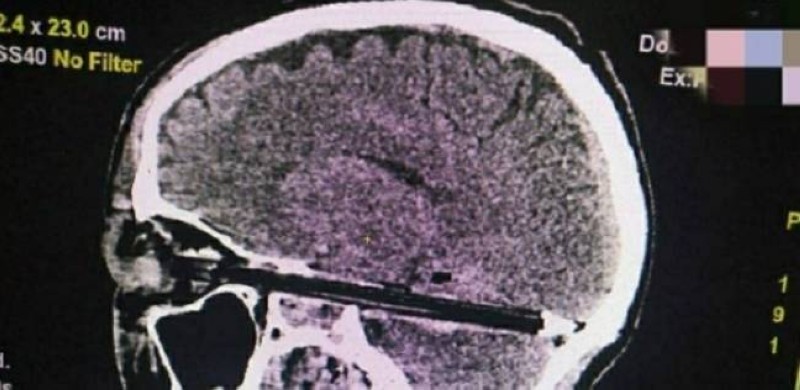

ووفق أطباء قسم الإسعاف بمنطقة روستوف الروسية، فإن القلم دخل العين بشكل كامل، ووصلت نهايته إلى مؤخرة الجمجمة، ومر مليمترات من الأوعية الدموية الرئيسية وجذع الدماغ، حسبما ذكرت «سبوتنيك».

ومن غير المعروف كيف دخل القلم إلى الجمجمة، والمريض حاليا في العناية المركزة وخضع بعد العملية للأشعة المقطعية للوقوف على حالته في حالة تعرضه لأي ضرر عصبي بعد سحب القلم من المخ.